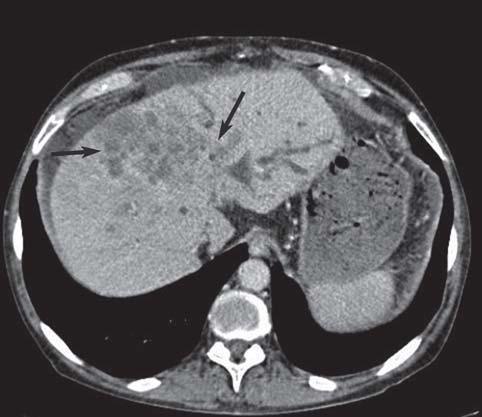

- КТ или МРТ — показывают полную картину болезни — локализация всех метастазов — данное исследование необходимо при проведении операции.